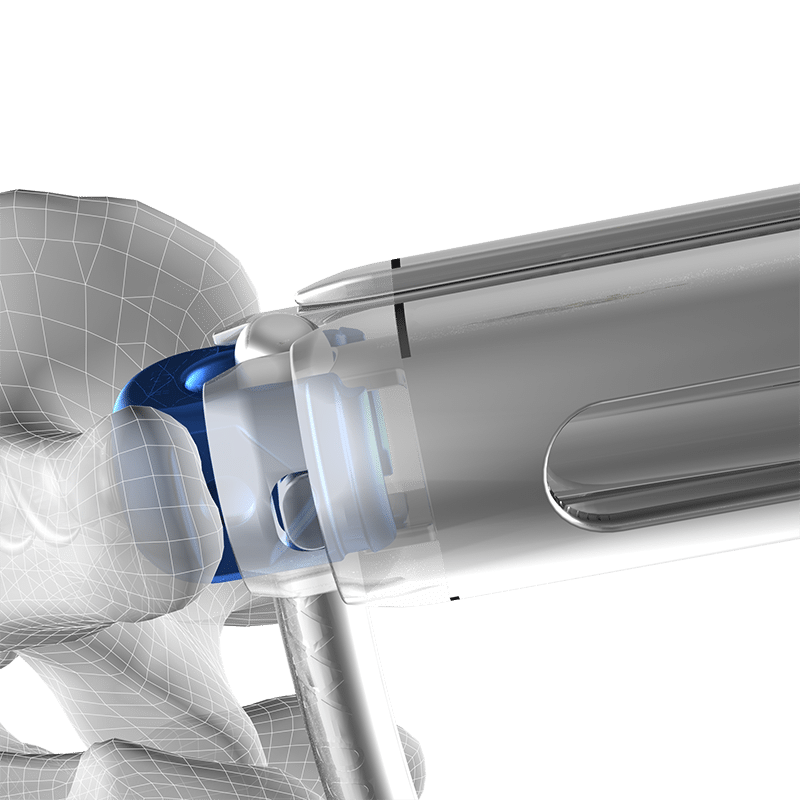

- 4 methods of rod reduction

- Lateral & inline rod connectors

- Side-to-side, end-to-end, and wedding band connectors